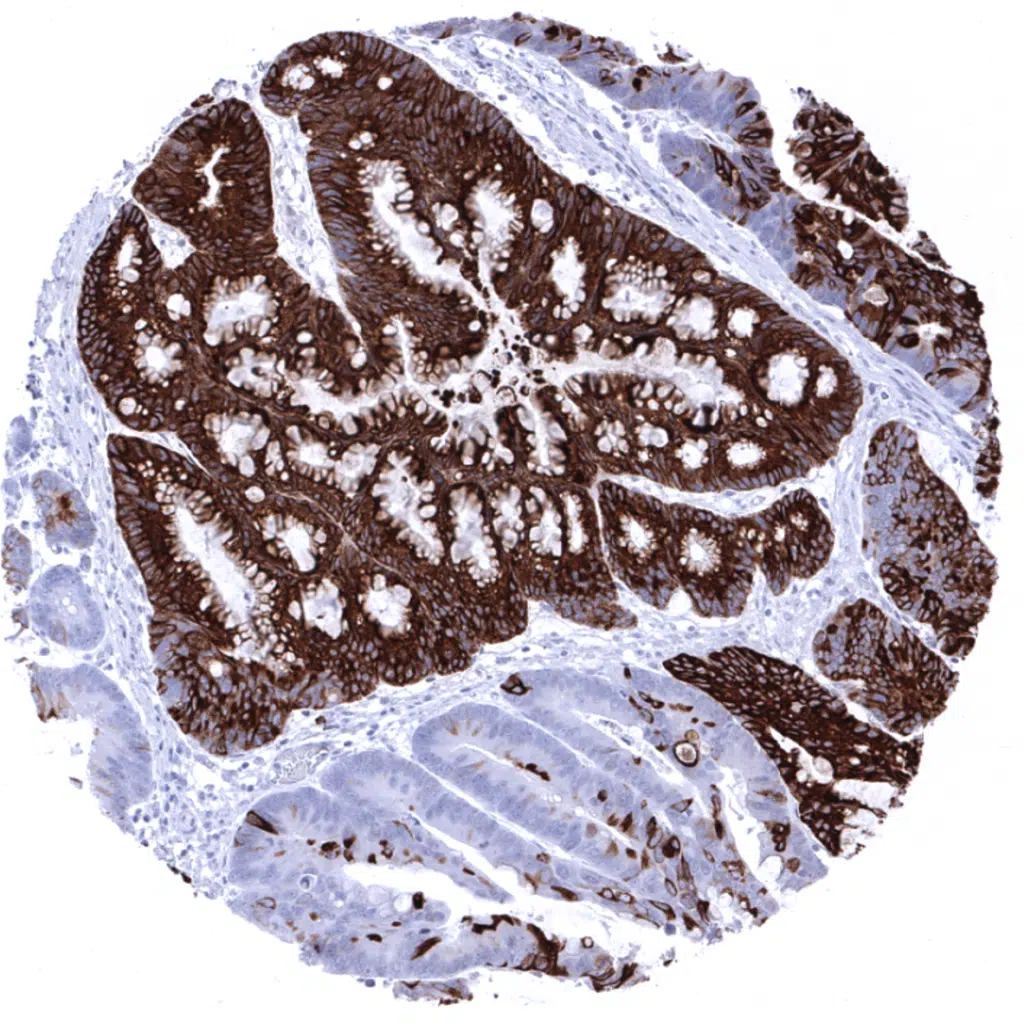

Colon- Strong diffuse MUC5AC immunostaining in a colorectal adenocarcinoma.

Colon- Strong diffuse MUC5AC positivity in a colorectal adenocarcinoma exhibiting an intestinal type growth pattern.